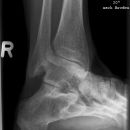

• Einteilung der OSG-Frakturen nach Danis-Weber: Höhe der Fibulafraktur in Bezug zur Syndesmose =>

"Weber A" : Außenknöchelfraktur infrasyndesmal +/- Innenknöchelfraktur; Syndesmose intakt

"Weber B" : Außenknöchelfraktur transsyndesmal +/- Innenknöchelfraktur; Syndesmose meist teilrupturiert

"Weber C" : Außenknöchelfraktur suprasyndesmal +/- Innenknöchelfraktur; komplette Sydesmosenruptur und Ruptur der Membrana interossea bis auf Frakturhöhe

Trimalleoläre Fraktur: bimalleoläre OSG-Fraktur mit Fraktur des Volkmann-Dreieck

Einteilung der Talushalsfrakturen nach Hawkins